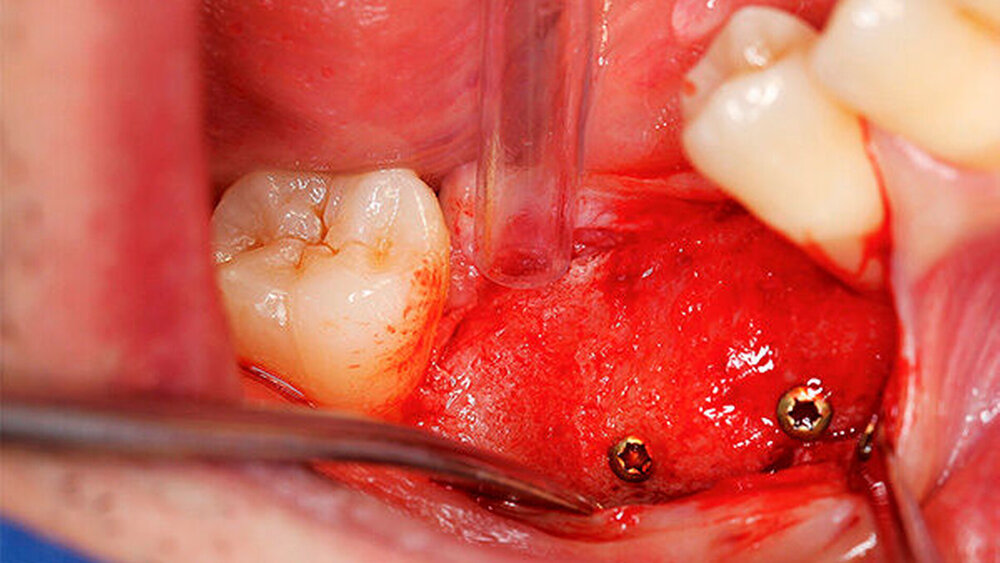

Ein 29-jähriger Patient stellte sich mit einer massiven Alveolarkammatrophie im rechten Unterkiefer in unserer Praxis vor. Diese lag in langen Jahren der Zahnlosigkeit begründet. Eine Beckenkammaugmentation kam für den Patienten nicht in Betracht. Dennoch wünschte er die Versorgung mit festsitzendem Zahnersatz. Nach ausführlicher Beratung entschied sich auch dieser Patient für eine Augmentation mit einem patientenindividualisierten allogenen CAD/CAM-gefertigten Knochenblock. Die DICOM-Daten des Unterkiefer-DVTs wurde an die Firma Zimmer gesendet, und es erfolgten wie im oben beschriebenen Fall eine virtuelle Planung und das virtuelle Design des allogenen Knochenblocks anhand der geplanten Implantatpositionen. Nach der üblichen Kontrolle und Freigabe des Chirurgen erfolgte die eigentliche Fertigung und Übersendung des Knochenblocks in die Praxis. Die Augmentation erfolgte auch in diesem Fall in Vollnarkose unter antibiotischer Abschirmung perioperativ mit Ampicillin. Die Schnittführung im Unterkiefer unterscheidet sich von der Sockelschnittführung im Oberkiefer aufgrund der Anatomie (N. mentalis). Auch bei diesem Patienten wurde eine tief im Vestibulum liegende bogenförmige Inzi‧sion durchgeführt, jedoch ohne die vertikalen Entlastungen. Nach streng subperiostaler Präparation erfolgte die Darstellung des N. mentalis. Die Vorbereitung des Spenderbetts sowie die Wässerung, Einpassung und Befestigung des allogenen Knochenblocks gestalteten sich wie im Fallbeispiel 1. Die Heilzeit des Knochenblocks dauerte ebenfalls sechs Monate. Zwei Implantate (Straumann) wurden nach krestaler Schnittführung in Lokalanästhesie eingebracht und heilten subgingival binnen drei Monaten ein. Aufgrund des massiven Volumenzuwachses war auch ebenfalls eine Vestibulumplastik im Zuge der Implantatfreilegung notwendig. Das Prozedere verlief ebenfalls wie im Fallbeispiel 1. Das freiliegende Gewebe wurde mit einer Kollagenmatrix abgedeckt. Dadurch konnte die Breite der befestigten Gingiva deutlich verbreitert werden.